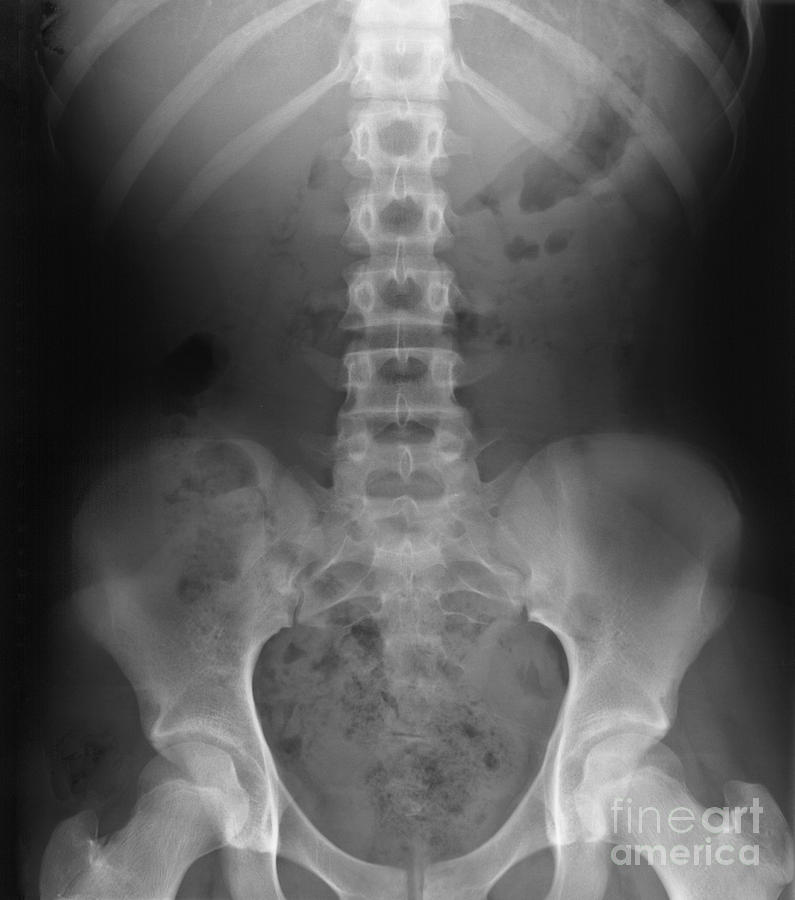

The Essential Role of X-Rays in Ensuring Safe and Effective Chiropractic Care

Chiropractic care plays a vital role in promoting good health, alleviating pain, and addressing muscle and bone issues. X-ray imaging is necessary for your Chiropractic doctor to better understand the spine and musculoskeletal structures, prevent harmful adjustments and to optimize treatment results.